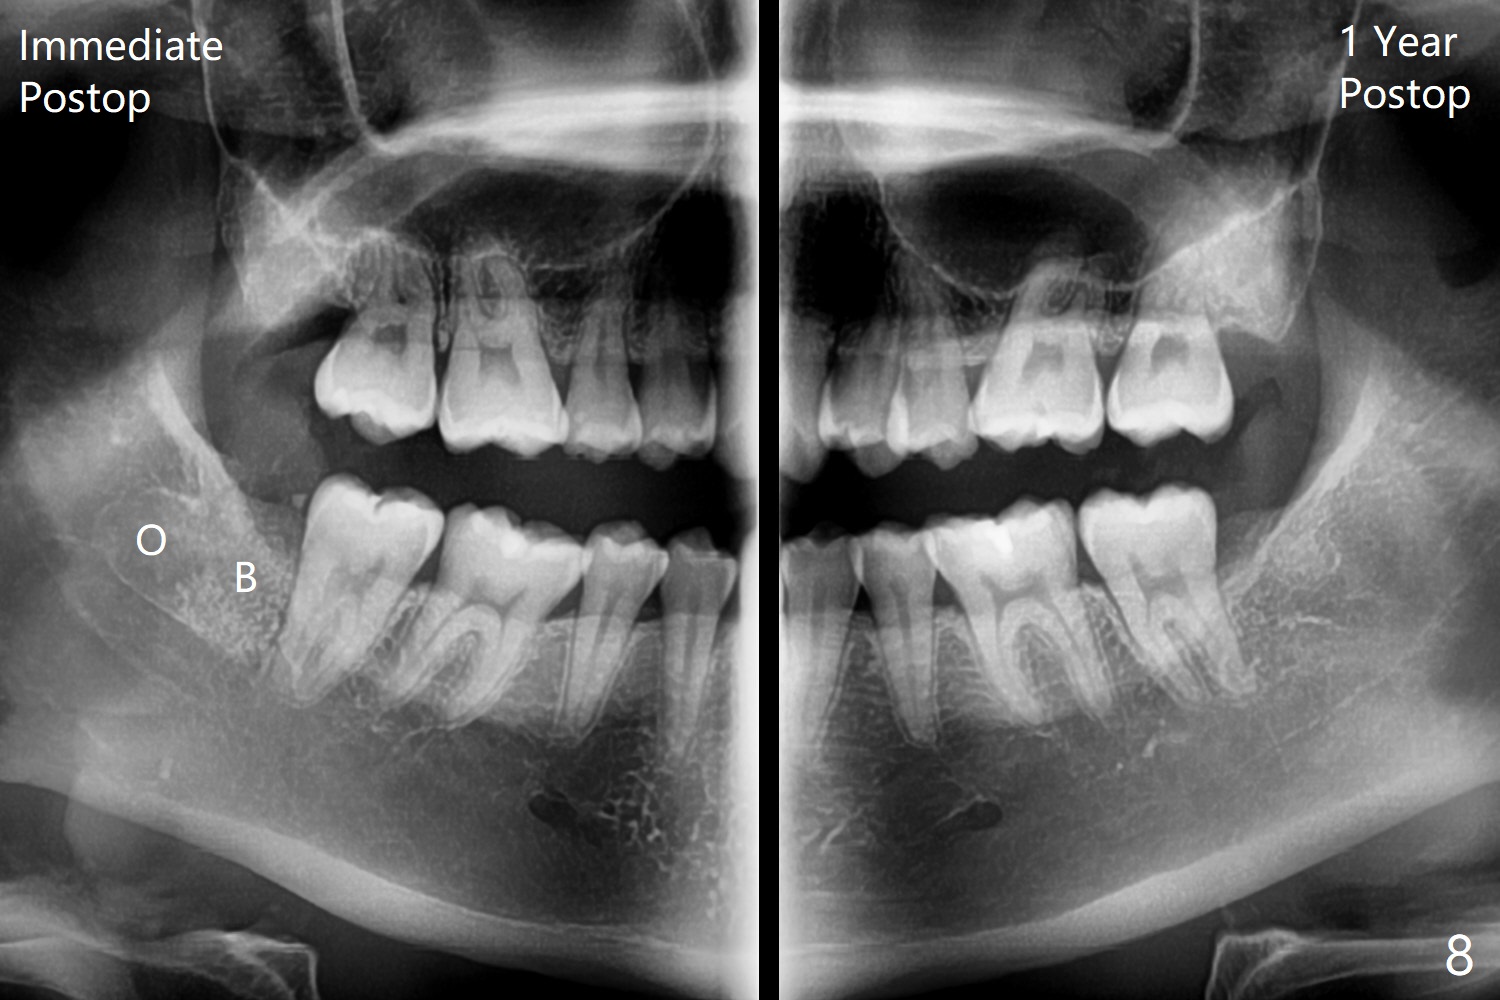

A 25-year-old woman, under our care for the last 11 years (Fig.1-6), returns for #1 and 32 extraction (1 year after #16 and 17 extraction (Osteogen plug)). Preop PA shows that a portion of the lower impacted tooth may be located buccal to the tooth #31 (Fig.4 black dashed line). An accessory incision is moved from distobuccal to midbuccal (Fig.7 arrowheads) to reduce postop loss of bone graft (Fig.8 B) from the incision. In fact the incision should be further moved to mesiobuccal (Fig.9 red line) if buccal impaction is suspected (curved black line). The buccal impaction of #32 of her father is more severe.